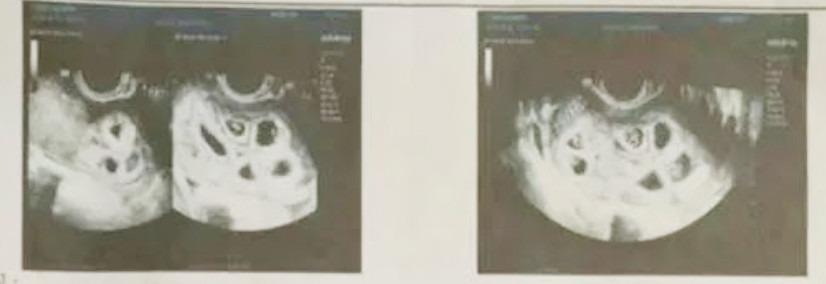

Ngày 12/11, cô đến bệnh viện kiểm tra thì thấy có tới 9 túi thai nằm sát nhau, có sự tách biệt rõ ràng. "Lúc đó, khi biết mình có thai, tôi cảm thấy rất vui mừng. Ước mơ làm mẹ của tôi đã thành hiện thực. Tôi nghĩ mình có thể sinh đôi nhưng không ngờ có 9 bào thai", cô Hầu chia sẻ.

Cô Hầu không nghĩ mình có thể mang thai cùng lúc 9 đứa con. Ảnh: Nhân vật cung cấp